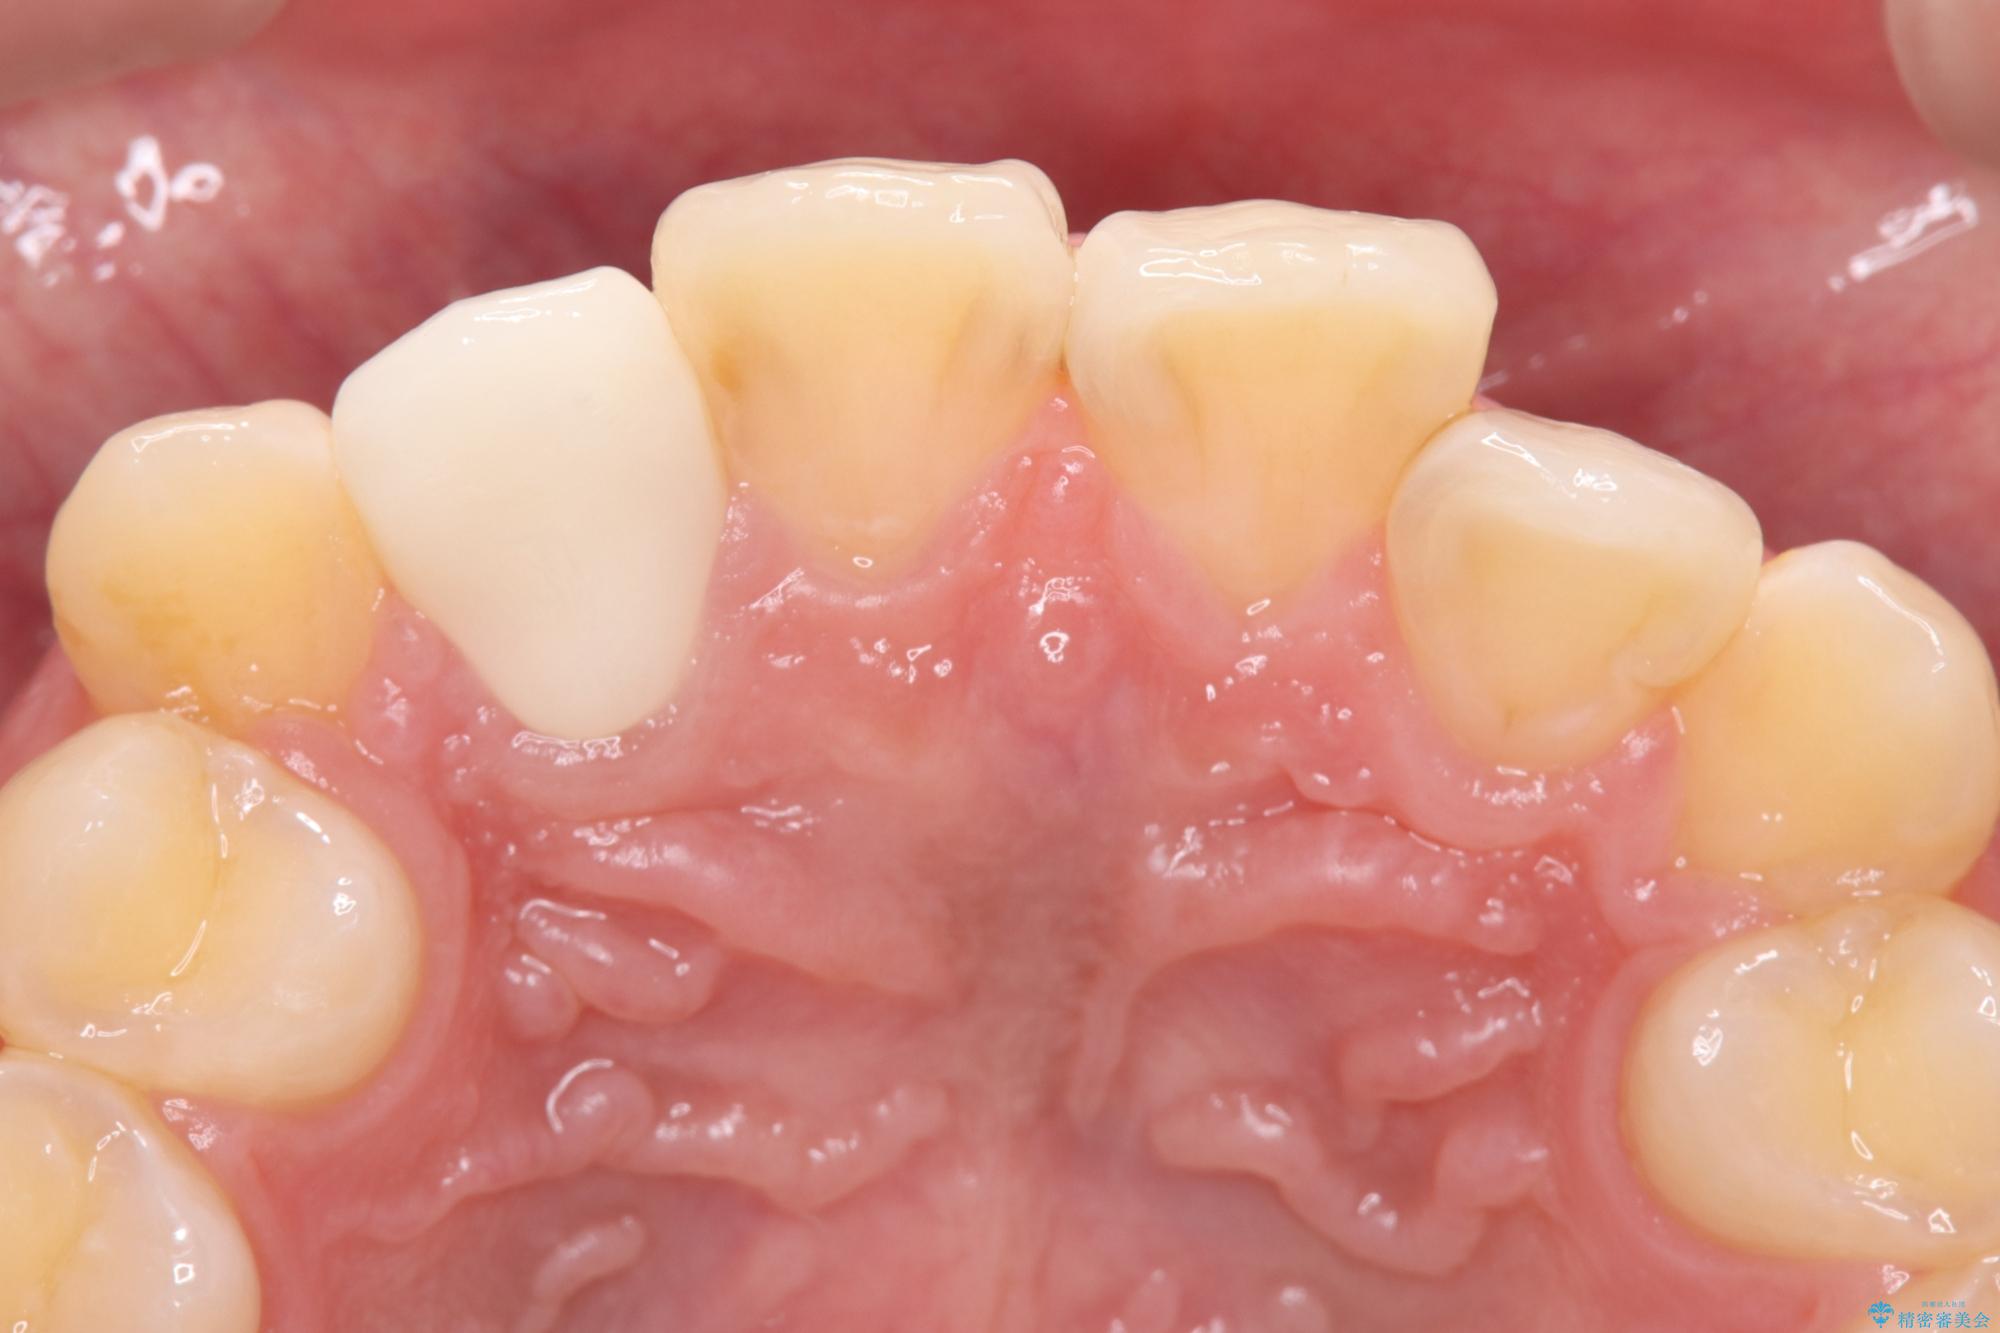

- 主訴:右上の前歯が何しなくても痛い

右上2番の歯に自発痛を認め、症状や歯髄診・レントゲン像から不可逆性歯髄炎と診断し、精密根管治療から歯冠補綴まで行うこととなりました。

初診時に歯髄診断を行い、不可逆性歯髄炎と診断し抜髄から補綴修復までの流れを説明し、精密根管治療、ファイバ-コア築造、オールセラミッククラウン(St)修復を行うこととしました。